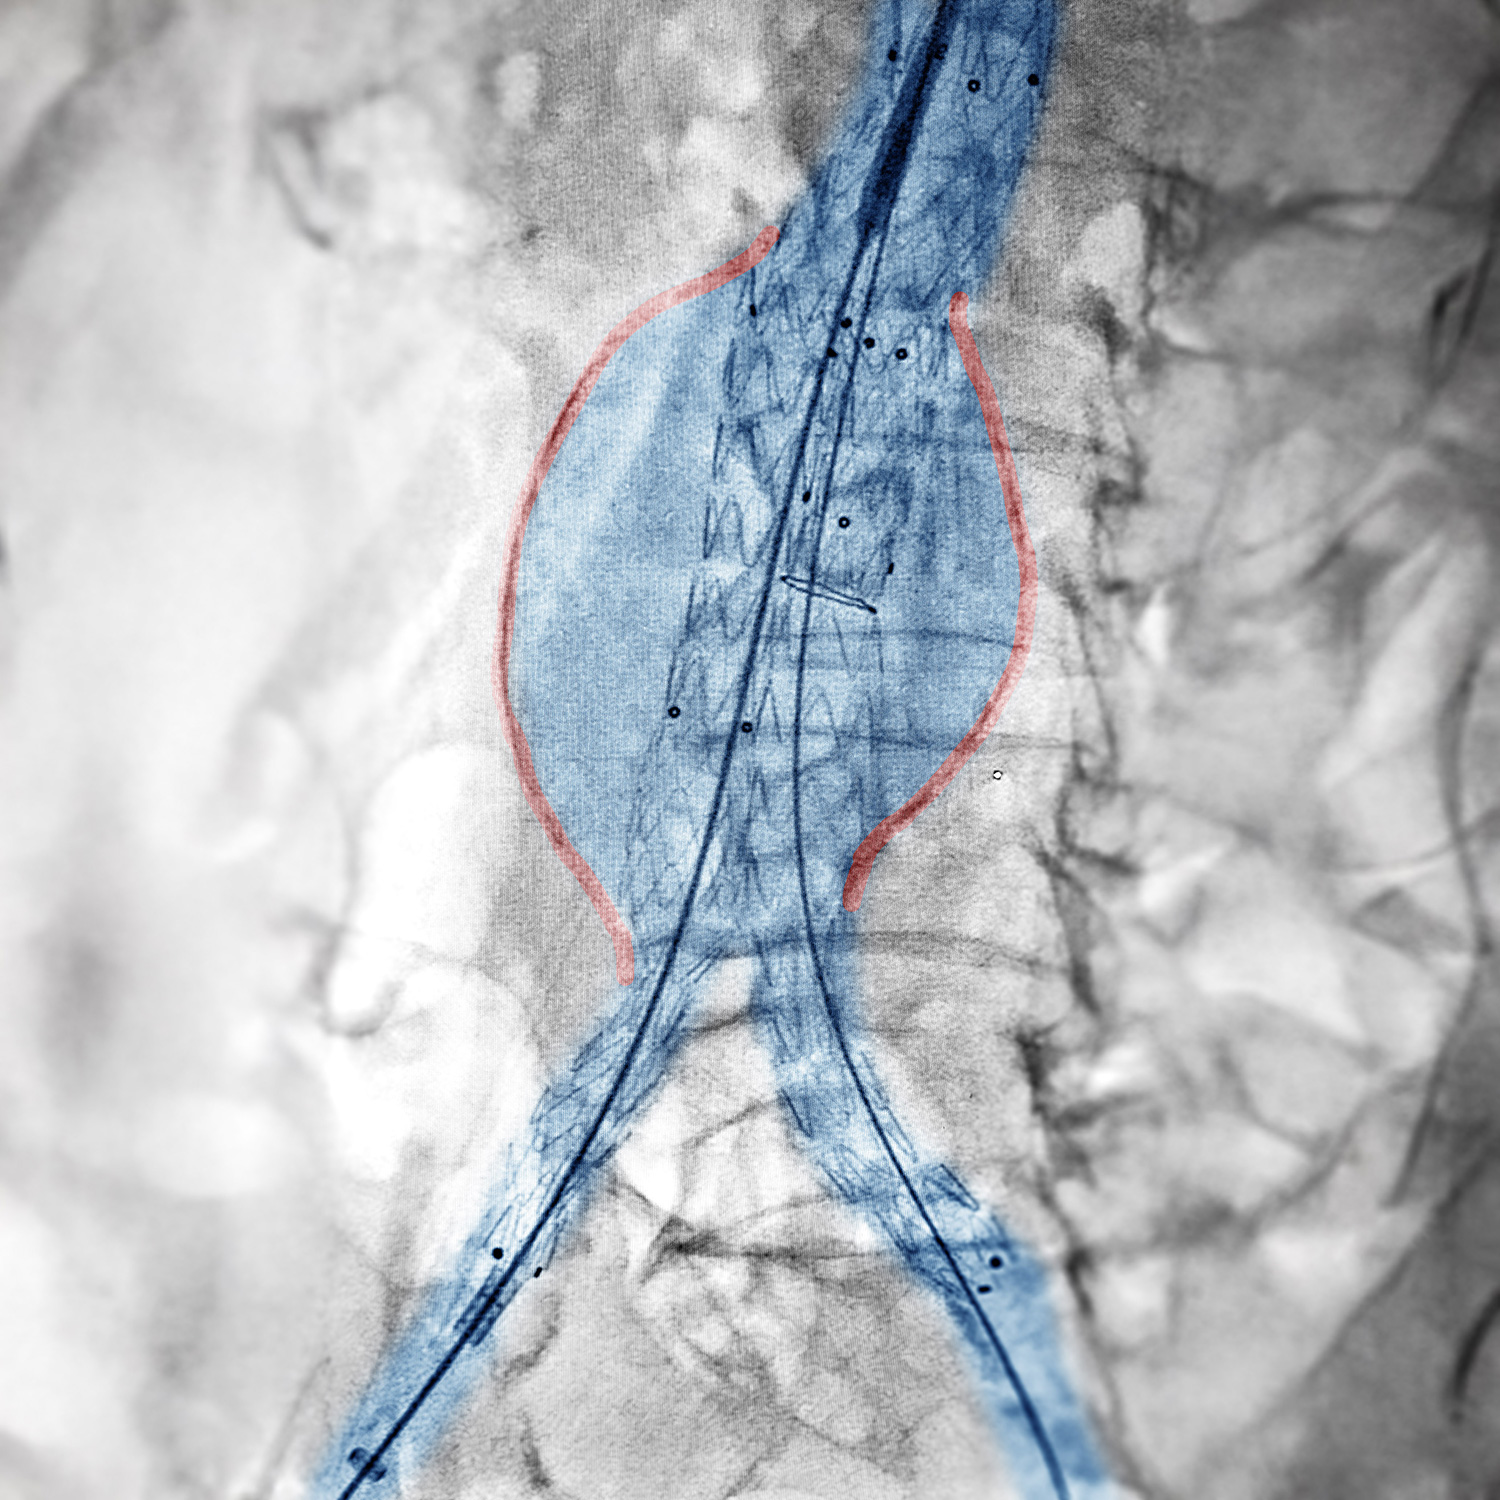

Auf dem beigefügten Bild ist das behandelte Aneurysma, also die Aussackung rot gekennzeichnet, die Bauchaorta in hellblau dargestellt und das individuell auf den Patienten abgestimmte Implantat erkennbar. Dieser Eingriff demonstriert die fortschrittliche Medizintechnik und die Fähigkeit der Klinik, patientenspezifische Lösungen anzubieten.

Die sogenannte EVAR ist eine minimalinvasive Methode zur Behandlung eines Aortenaneurysmas, also einer gefährlichen Aussackung in der Bauchschlagader, bei der ein spezielles Implantat, ein sogenannter Stentgraft (eine Art Stützgerüst), über die Blutgefäße in die Aorta eingeführt wird, um die erweiterte Stelle zu stabilisieren und einen Riss der Gefäßwand zu verhindern. Durch diese Technik kann in vielen Fällen eine aufwändige offene Operation vermieden werden, was die Genesungszeit und das Risiko für die Patienten deutlich reduziert.

Derartige Eingriffe werden am Klinikum neuerdings in der neuen interdisziplinär genutzten Biplanen Angiografieanlage durchgeführt. Diese hochmoderne Durchleuchtungsanlage bietet eine exzellente Bildgebung, die den Chirurgen eine präzise Navigation und Planung während des Eingriffs ermöglicht. Die verbesserte Bildqualität erleichtert die Arbeit des chirurgischen Teams erheblich und trägt dazu bei, die Behandlungsqualität für die Patienten weiter zu steigern.